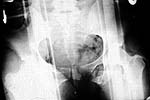

The patient sustained multiple injuries 11 months previously, including the pelvic ring disruption seen in the attached photos. The anterior injury was a fracture through the left pubis; the posterior lesion was a vertical fracture of the sacrum.

Initially an exfix was used at a university hospital trauma center.

Four months later bilateral iliosacral screws were used for an apparent nonunion of the sacral fracture.

An exfix was reapplied two months thereafter, apparently to try to reduce the now widened anterior pelvic ring defect. It was removed after a short period of time, probably because it was ineffective. The orthopaedic surgeon told her that he would not fix the anterior pelvis under any circumstances.